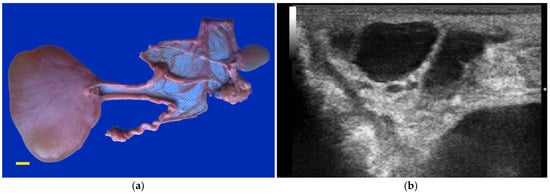

Ovarian dysgenesis/hypoplasia was diagnosed in 36.3% of maiden SACs presented for infertility. This is higher than the 16.8% incidence reported in slaughtered alpacas that were culled for infertility [17]. The high incidence in our data may be due to the inability of referring veterinarians to diagnose these defects. Affected females are generally presented for repeat breeding without evidence of ovulation. In rare cases, the female may be presented due to male rejection in the absence of a pregnancy or a rise in progesterone level. The disorder is characterized by the lack of normal follicular activity, difficulty in visualizing the ovary by ultrasonography, and an infantile reproductive tract [7,18]. Confirmation of the diagnosis is achieved via laparoscopy (Figure 1). Hormonal diagnosis (i.e., serial serum estradiol concentration, anti-mullerian hormone (AMH) concentration) is possible but rarely performed. The ovaries are extremely small, measuring 2 to 3 mm in length. Histologically, this syndrome can be categorized as ovarian hypoplasia (i.e., germ cell deficiency or low germ cell resistance), ovarian dysgenesis (i.e., defective embryonic development of the gonad), or ovarian dysplasia (i.e., abnormal follicular development) [18].

Figure 1. (a) Reproductive tract (scale bar: 1 cm) and (b) laparoscopic view of an alpaca with ovarian dysgenesis. Arrows indicate ovaries; (c) Histology of ovarian hypoplasia in an alpaca (scale bar: 2 mm).